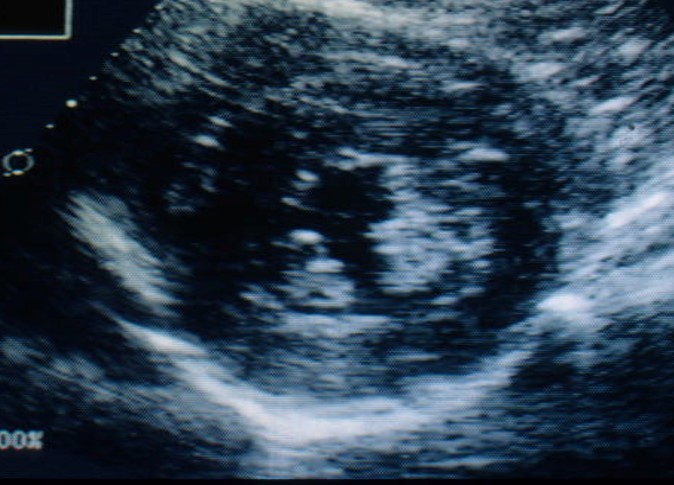

What can be seen?

A short-axis

(cross sectional)

view of the L ventricle shows a thick LV free wall and a thick interventricular septum